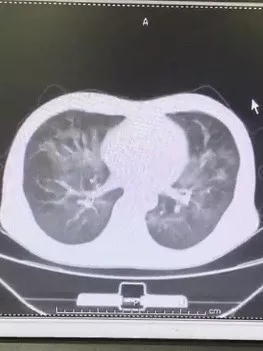

一周前 , 50岁的老吴因咳嗽不断、高烧不退 , 去发热门诊开了抗炎退烧药 。 吃了2天后 , 情况有了好转 , 但高烧一直退不下来 。 没多久 , 咳嗽又开始加重 , 老吴决定去输液 。 医生了解情况之后 , 让老吴去复查CT 。 CT结果显示 , 老吴的肺炎正在逐渐加重 。

文章插图